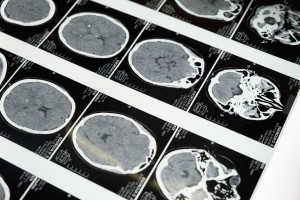

Alzheimer kategorisi, yaşlılık döneminde görülen ilerleyici bir sinir sistemi hastalığı olan Alzheimer'ın belirtileri, teşhisi, tedavisi ve hastalığın bireyler ve aileler üzerindeki etkilerini ele alır.

Alzheimer hastalığı, yaşlılık döneminde ortaya çıkan, ilerleyici bir sinir sistemi hastalığıdır ve en yaygın görülen demans türlerinden biridir. Alzheimer kategorisi, bu hastalığın belirtileri, teşhisi, tedavisi ve hastalığın bireylerin ve ailelerinin yaşam kalitesine olan etkileri gibi konuları ele alır. Bu kategori, Alzheimer hastalığının genel bir anlayışını sunarken, aynı zamanda bu hastalığın toplumda yarattığı farkındalığı artırmak amacıyla hazırlanan içeriklere de ev sahipliği yapar.